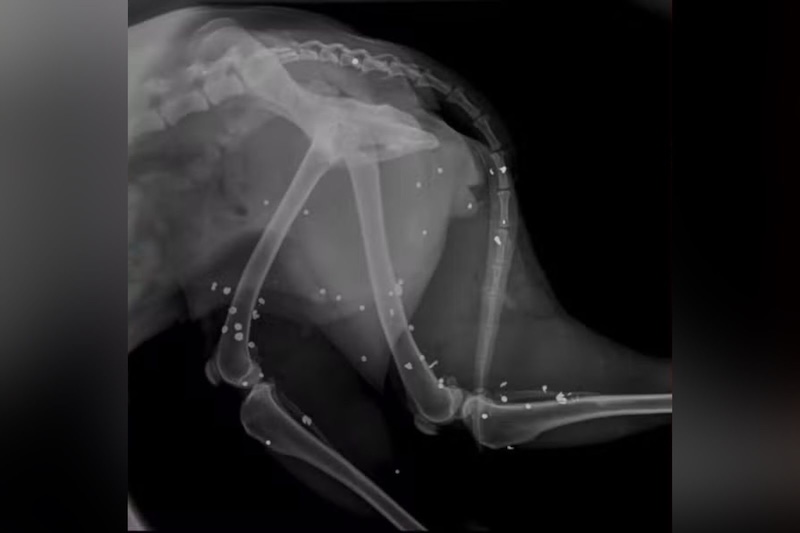

O animal que sobreviveu foi resgatado e encaminhado com urgência para atendimento na clínica veterinária particular. Exames de raio-x apontaram que a cadela foi atingida por 43 chumbinhos — tipo de munição —, espalhados pelo corpo e próximos a órgãos vitais.